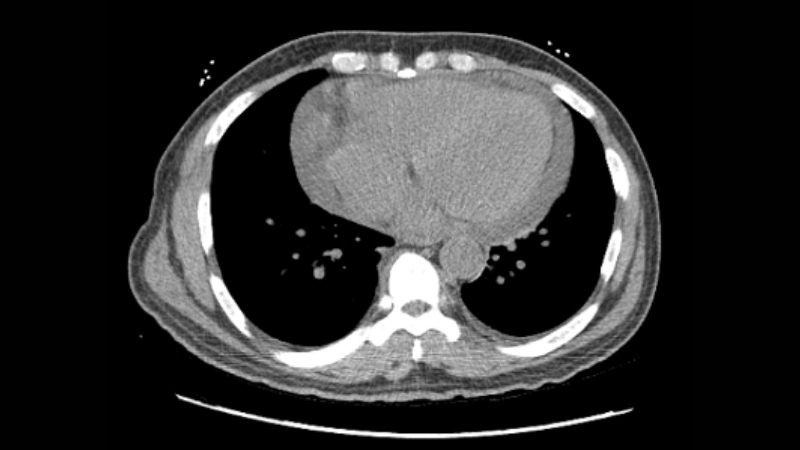

Image description of Human T-lymphotropic Virus (HTLV) Infection

A microscopic image of HTLV shows the virus attacking white blood cells, emphasizing its effect on the immune system and potential long-term health complications.